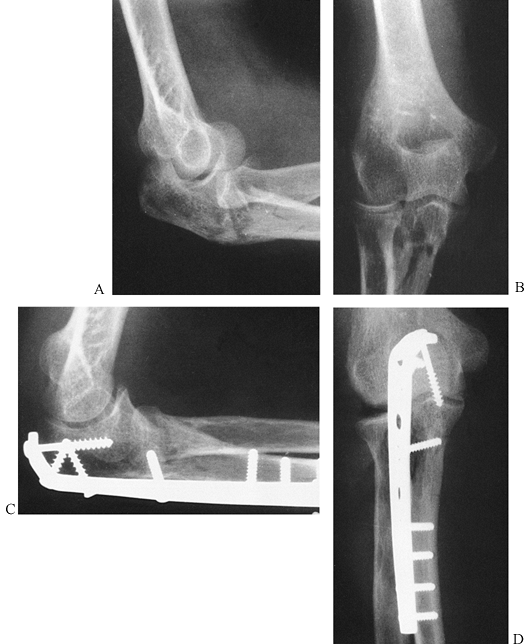

![]() |

Figure 16.12. A:

A type III olecranon fracture in which the proximal fragment is insufficient for plating. Gross instability with anterior subluxation of the radius and ulna is noted at the time of surgery. B: Fixation using an intramedullary cancellous screw and tension band wiring. |

(comminuted) injury, the fracture is frequently complex and is usually

a challenge to reduce and fix (Fig. 16.13). If

the fracture extends beyond the coronoid process, length must be

restored. Fractures of the coronoid process must be adequately reduced

and fixed to preserve stability (117). Reconstruct the joint surface using interfragmentary screw compression wherever possible. Bone graft is

frequently needed. Then contour a 3.5 to 3.7 mm reconstruction plate to

fit along the posterior–lateral cortex to buttress the fragments and

help neutralize the deforming forces (Fig. 16.13C, Fig. 16.13D). A semitubular plate is usually too weak (152). Other possibilities for fixation include tension band wiring and the use of modified plates such as the hook plate (173).